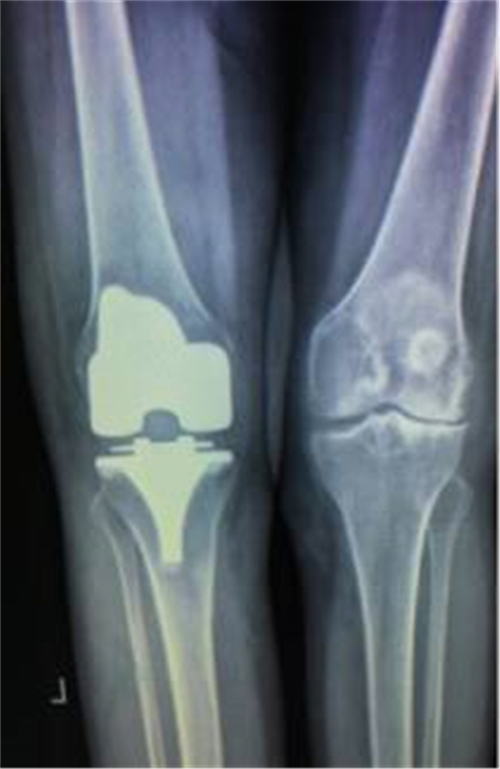

经过与家属的耐心沟通,谭宜昌主任及其团队决定为谢某实施膝关节置换手术。8月25 日上午,谭主任及其团队历时90分钟,成功为患者实施了膝关节置换术。术后患者的膝关节畸形矫正,膝关节稳定性也已恢复,膝关节功能明显改善。出院时谢某脸上洋溢着满意的笑容,说非常感谢谭主任团队把折磨自己多年的疾病给治好了。

术后X线